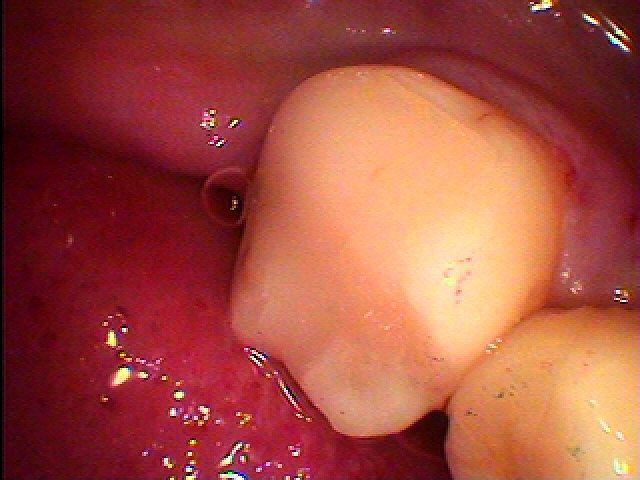

銀歯の下は基本このように悪くなっていることが多いです。| |広島市安佐南区の歯科医院 銀歯の下は基本このように悪くなっていることが多いです。 トップ お知らせ・ブログ 銀歯の下は基本このように悪くなっていることが多いです。 銀歯の下は基本このように悪くなっていることが多いです。 Web診療予約 初めての方へ 選ばれ続ける理由 院内設備について 歯が痛いしみる一般歯科 歯がぐらぐらする歯周病 健康な歯を保ちたい予防歯科 子供の虫歯予防をしたい小児歯科 銀歯をセラミックに審美歯科 白い歯を目指しませんか?ホワイトニング 矯正専門医がいるので安心矯正歯科 抜けた歯を補いたいインプラント・入れ歯 医院案内 スタッフ紹介 メリィハウス歯科クリニックオフィシャルホームページ ラベンダー歯科クリニックオフィシャルホームページ お知らせ・ブログ ホーム 診療科目 一般歯科 歯周病治療 予防治療 小児歯科 審美治療 ホワイトニング 矯正歯科 入れ歯・インプラント マウスピース矯正 初めての方へ 院長・スタッフ 設備紹介 医院案内・アクセス メニューを閉じる